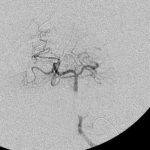

'19年5月

30代

富永/久貝

右中小脳脚 出血再発

SM 3(S1,E1,V1)

米国の病院

No.359 モニタリング

No.359 手術前

No.359 手術中

No.359 手術後

出血既往があり。2回の手術前血管内手術の後に、

Lateral transpeduncular approachにより再々出血予防を目的に

摘出手術を行う。完全摘出であることを確認した。

手術による合併症や後遺症なしで退院した。経過良好。